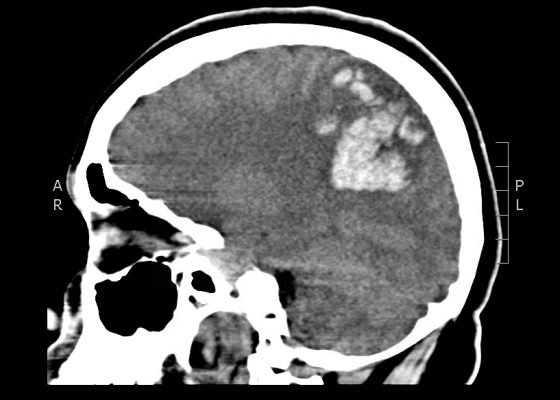

Intracranial Hemorrhage Following a 3-week Headache

DOI: https://doi.org/10.21980/J89885The patient’s head CT showed a significant area of hyperdensity consistent with an intracranial hemorrhage located within the left frontal parietal lobe (red arrow). Additionally, there is rightward midline shift up to 1.1cm (green arrow) and entrapment of the right lateral ventricle (blue arrow).